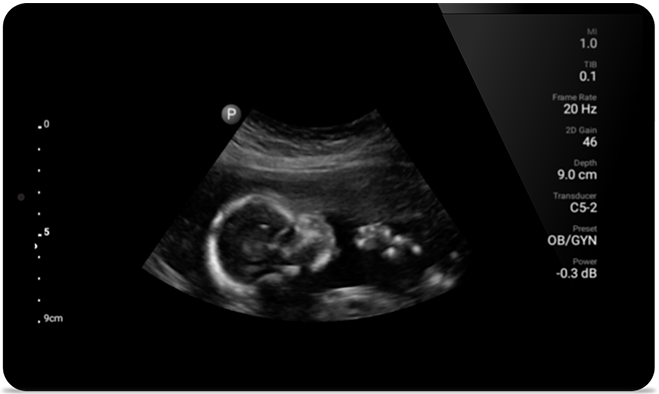

• Rango extendido de frecuencias de 5 a 2 MHz • Radio de curvatura de 50 mm • 2D, Doppler a color, Modalidad M, XRES avanzado e imágenes armónicas multivariables, SonoCT • Imágenes de alta resolución para aplicaciones más profundas: optimizaciones preestablecidas de imágenes abdominales, de vesícula biliar, gineco-obstétricas y pulmonares • Marcador de línea de centro • Transductor USB-C con cable reemplazable

Desde revelar los detalles sutiles de una imagen hasta descubrir la definición del tejido enriquecido desde múltiples ángulos, Lumify puede ayudarlo a tomar decisiones en tiempo real con más confianza desde la evaluación hasta la recuperación.